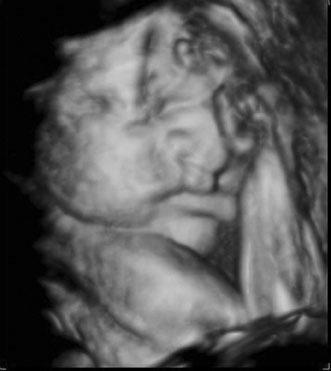

A second trimester ultrasound is usually done at 20 to 22 weeks' gestational age. The most commonly used fetal measurements are biparietal diameter, length of the femur or other long bones, and abdominal and head circumference. In addition to measurements, an anatomic survey is also done to evaluate the fetal brain (Fig. 9), spine, stomach, heart, kidneys, placental location and assessment of amniotic fluid (Fig. 10). If maternal risk factors are present, tetra screening results are abnormal, or there are abnormal findings on the anatomic survey, the patient is sent for a comprehensive ultrasound. The components of a comprehensive ultrasound are shown in Table 9. The ultrasound findings associated with Down syndrome include cardiac defects or enlargement, cystic hygroma (Fig. 11), duodenal atresia (Fig. 12), omphalocele, polyhydramnios, choroids plexus cyst, and renal calyceal dilation.

Fig. 10. Third trimester ultrasound image showing fetal ocular anatomy.